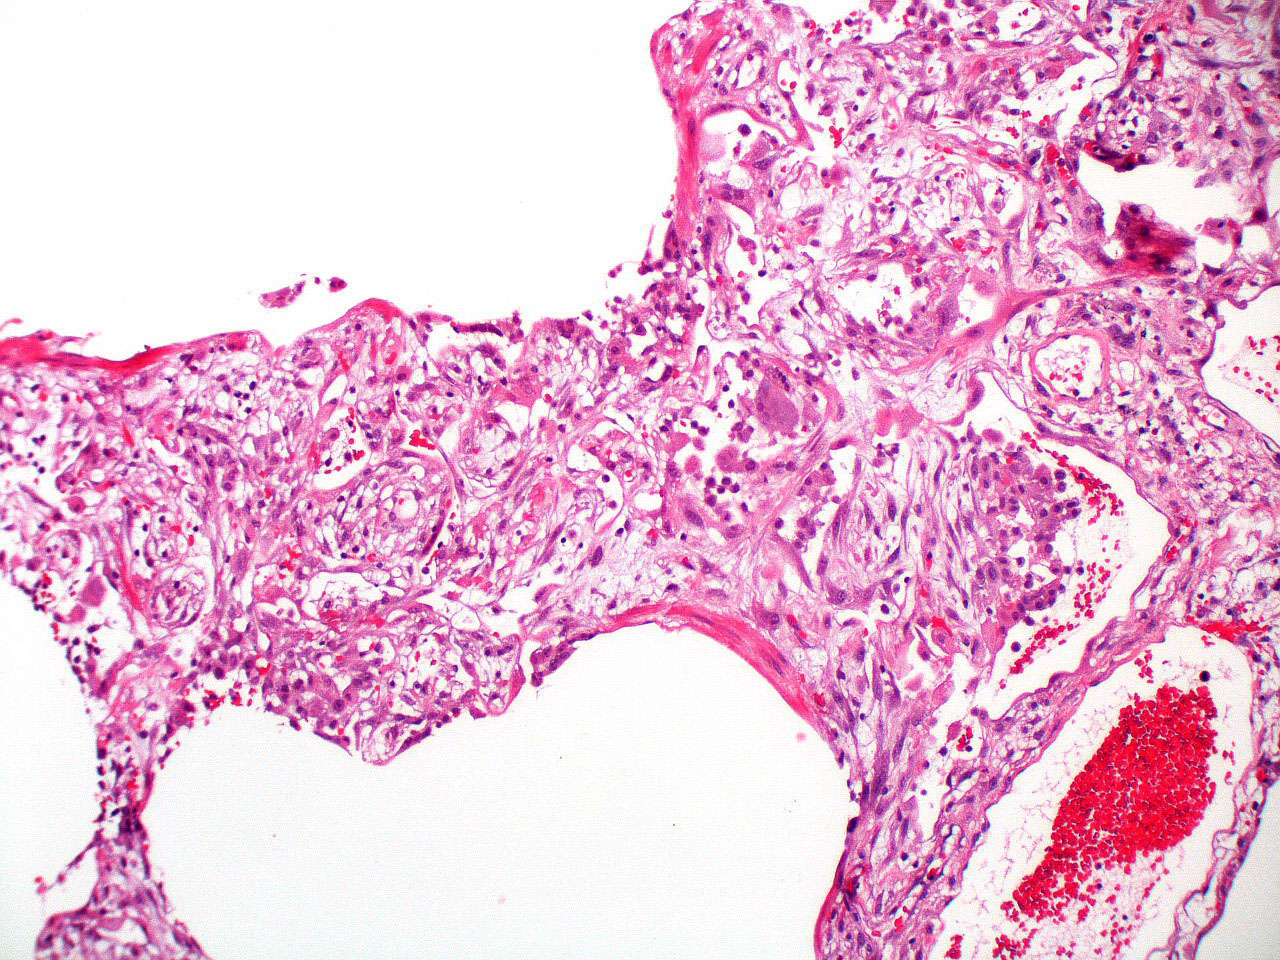

Microscopic (histologic) description

- Histopathology of DAD progresses from exudative (acute) phase through proliferative / organizing (subacute) phase to chronic fibrotic phase roughly corresponding to the period of ARDS (Am J Pathol 1976;85:209, Arch Pathol Lab Med 2010;134:719, Clin Chest Med 2000;21:435, N Engl J Med 2000;342:1334)

- Exudative (acute) phase

- Alveolar change

- Hyaline membranes on alveolar duct or sacs

- Interstitial and intra-alveolar edema

- Collapsed alveoli

- Epithelial change

- Denudation and necrosis of type I pneumocytes

- Vascular change

- Necrosis of endothelial cells

- Neutrophil aggregation

- Microthromboemboli

- Hemorrhage

- Alveolar change

Microscopic (histologic) images

Contributed by Akira Yoshikawa, M.D. and Yale Rosen, M.D.